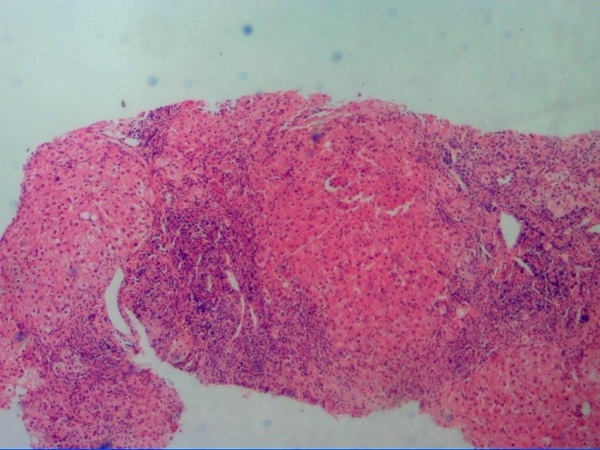

肝细胞坏死的指标经实验室检查从:可以从肝功,肝纤谱,肝脏超声,CT,病理检查上反映.

肝细胞坏死检查 近年证实,维生素A有延缓或阻止前病变,防止化学性致癌物作用,特别是防止上皮恶性肿瘤的

肝细胞坏死的检查有哪些?有问必答网肝细胞坏死症状查询频道为您解答肝细胞坏死的检查方面的知识,肝坏死是